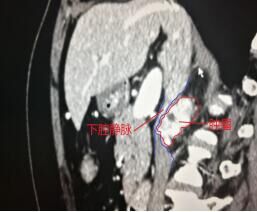

经过12天的充分术前准备,5月12日,由省立医院熊晖教授与副主任医师潘美洲主刀,为患者在全麻下行经腹腹腔镜下镜下腹膜后肿瘤探查、切除术。顺利建成气腹,建立工作通道,仔细完成既往腹腔术后腹腔内粘连的游离,充分暴露术区。谨慎游离各重要血管,在下腔静脉与右肾静脉夹角间作为突破口,开始仔细游离肿瘤,肿瘤触之易岀血,在吸引器吸引保持局部视野清晰条件下,沿肿瘤包膜仔细游离。游离过程中发现左肾动脉位于肿瘤的后上缘,肿瘤左侧与右侧肾上腺相邻,将其与右侧肾上腺分离,一点一点的将肿瘤自下腔静脉后方完整切除。顺利取出标本,手术顺利完成。麻醉满意,术中生命体征平稳,出血约100ml。